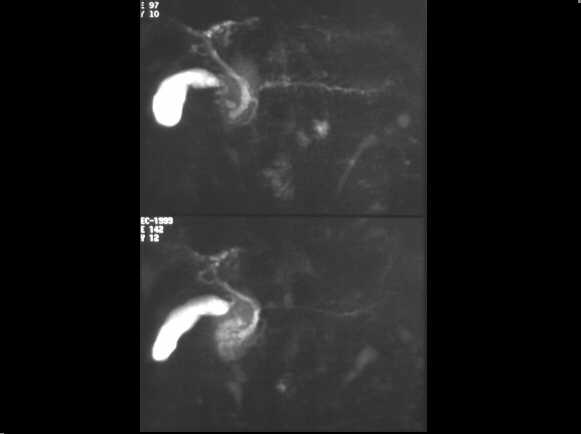

Obstructive chronic pancreatitis. MRCP examination demonstrates the chain of lakes pattern of the MPD. The CBD is also dilated.

Chronic pancreatitis before sphynterotomy.

MRCP examination demonstrates the chain of lakes pattern of the MPD. The CBD is

also dilated.

Same case after sphynterotomy. The MPD appears normal.